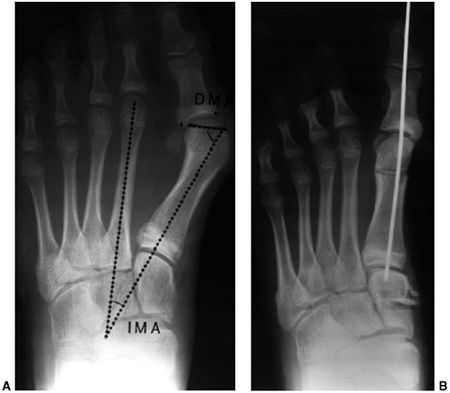

both clinically and radiographically in order to define healthy and

pathologic states. Radiographically, images are always taken in the

standing position, except in the case of infants, for whom position

should be specified. In standing anteroposterior and lateral views of

the foot, the following angles should be determined (Fig. 30.3):

Intermetatarsal angle (C)

(anteroposterior view) is the measurement of the angle subtended by the

long axis of the first and second metatarsal. This angle is generally

less than 5 degrees but is increased in deformities associated with

bunion formation (Fig. 30.3A). -

![]() |

|

Figure 30.3 The standard radiographs of the foot are taken in the standing position, anteroposterior and lateral views. A: On the anteroposterior view (A), the intermetatarsal angle (C) between the first and second metatarsal and the talocalcaneal angle (B) can be measured. B: On the lateral view of the foot, the lateral talocalcaneal angle, the Meary angle, the Hibb angle (D), and the calcaneal pitch (E) should be determined.